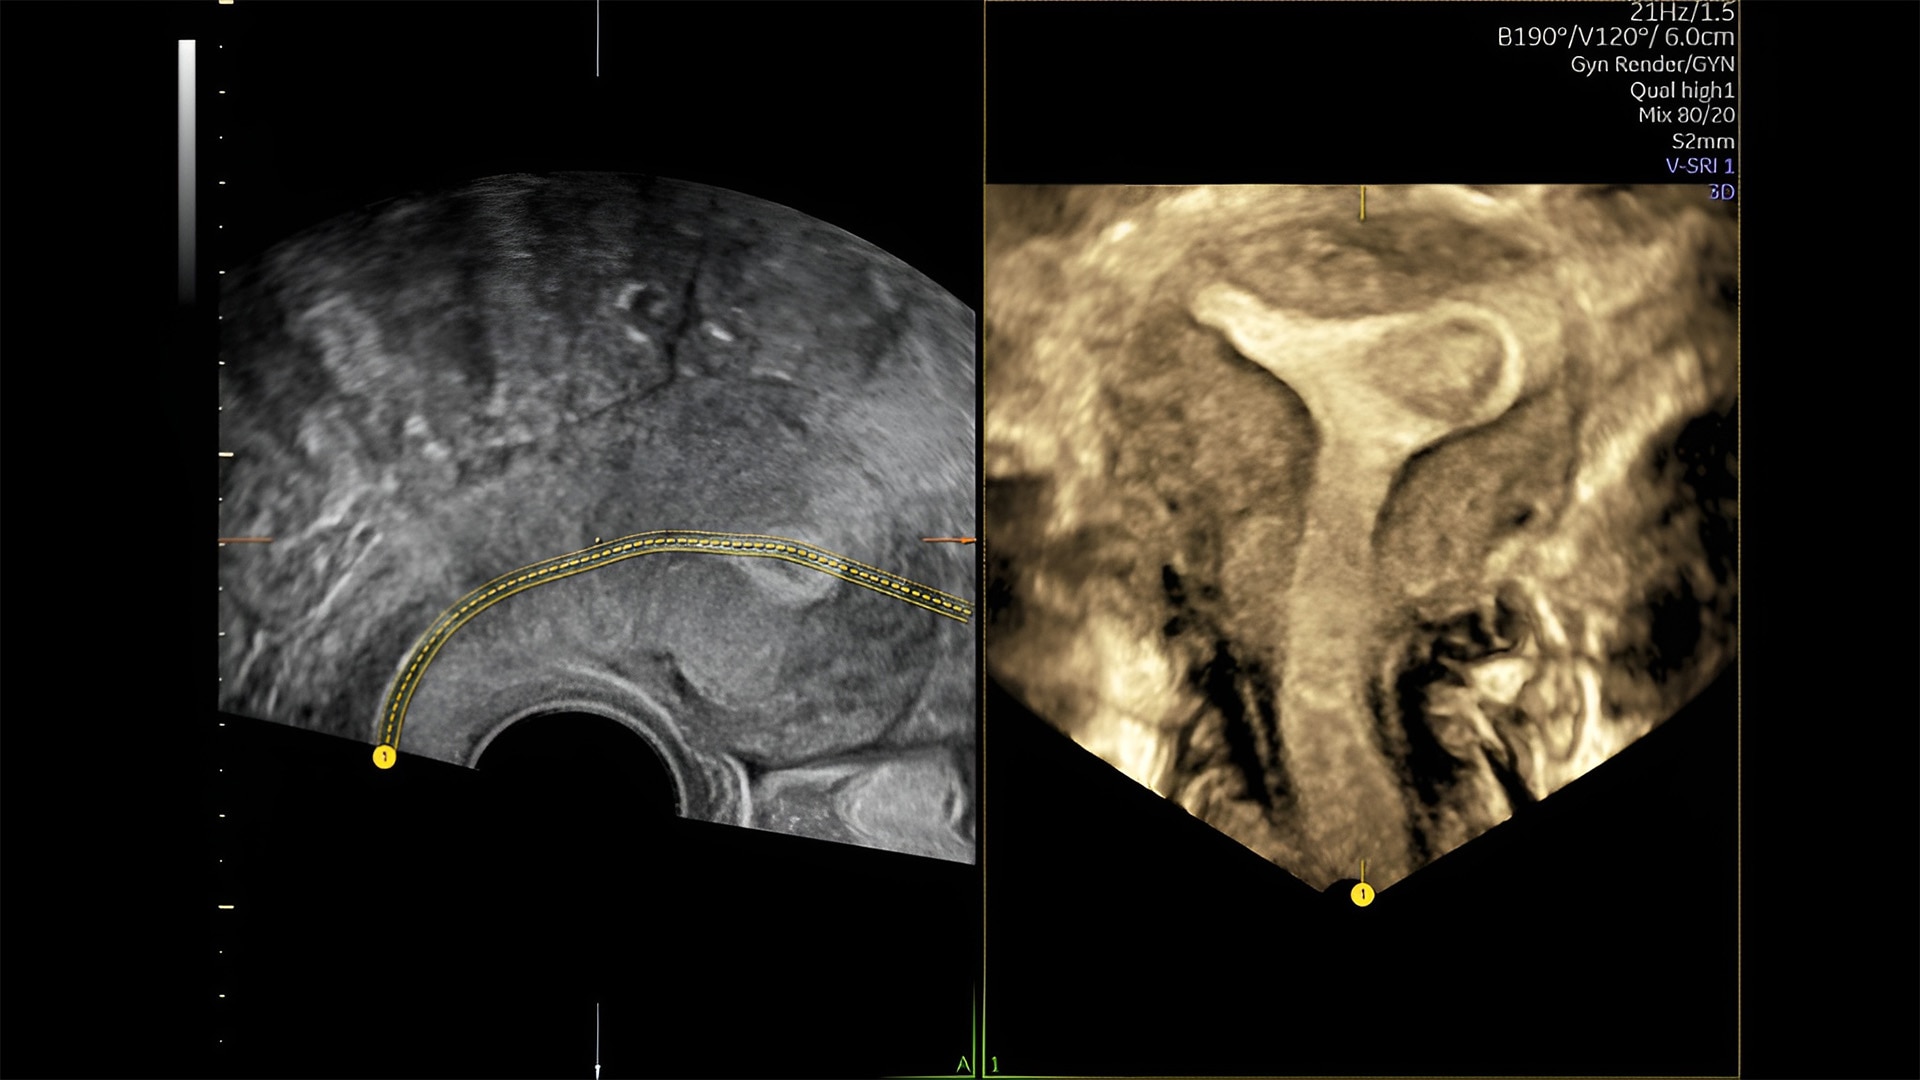

First trimester exams

Perform detailed exams with high-resolution for early insights to fetal health